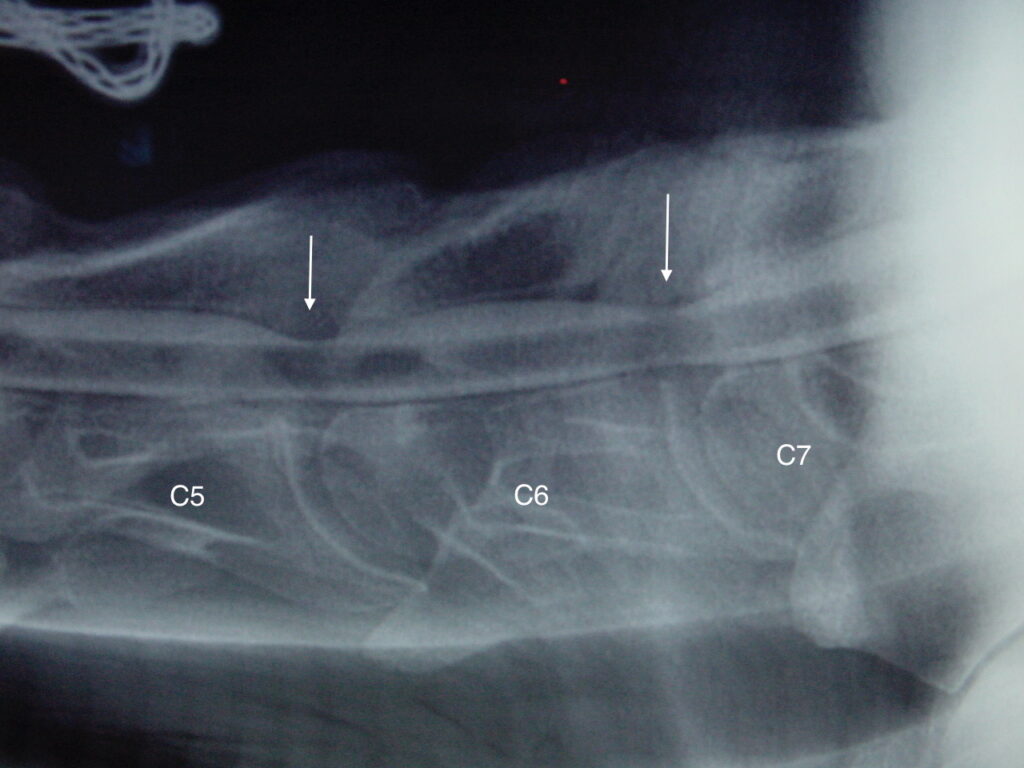

Obrázek 5: Rentgenový snímek krku s jasnou dynamickou kompresí na úrovni C5–C6, kontrastní látka téměř zmizela nad (červená šipka) a pod (bílá šipka) míchou

Proto se ataxie někdy projevuje pouze v okamžiku, kdy je kůň korektně ježděn na přilnutí, a dokonce v tu chvíli může začít i kulhat. Jakmile jezdec povolí otěže, kulhání vymizí. Naopak u koně se statickou kompresí (obr. 4) dochází ke stlačování míchy neustále, bez ohledu na polohu krku. V těchto případech dochází k závažnějšímu poškození míchy a kůň musí být léčen co nejdříve, aby nedošlo k trvalým následkům na míše.

Obrázek 4: Rentgenový snímek krku se statickou kompresí na úrovni C5–C6 a C6–C7, všimněte si zúžení sloupce kontrastní látky (bílá šipka) na povrchu míchy v těchto dvou místech